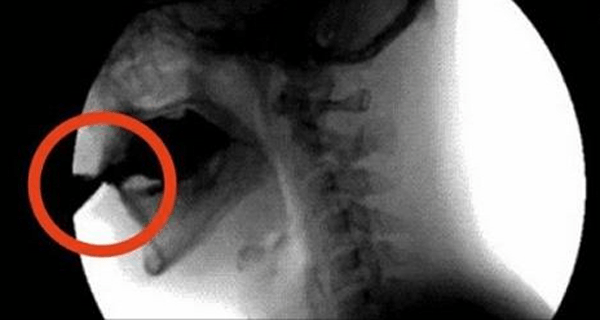

Kyselina fosforečná na seba viaže magnézium, zinok a vápnik. Veľké množstvo prijatého cukru a umelých sladidiel zvyšujú vyplavovanie vápnika z tela močom.

Kofeín má močopudné vlastnosti, ktoré sa začínajú prejavovať. Telo sa zbavuje magnézia, zinku a vápnika, dôležitých látok, ktoré mali smerovať do kostí. Rovnako aj sodík, voda a elektrolyty. Postupne začínate byť dosť podráždení a ospalí. Vylúčili ste vodu, ktorá mala byť využitá na tvorbu dôležitých látok, ktoré sú zodpovedné za hydratáciu tela a budovanie silných svalov a zubov.

Coca-Cola je jed, ktorý ničí kosti Mnohí si nie sú vedomí toho, čo všetko Coca-Cola dokáže spôsobiť v našom tele. Jej účinky nie sú vôbec pozitívne a okrem iného zvyšujú riziko vzniku diabetesu. Radšej si nalejte pohár čistej vody a ochuťte si ju napríklad citrónom, mätou alebo TU nájdete zopár tipov.